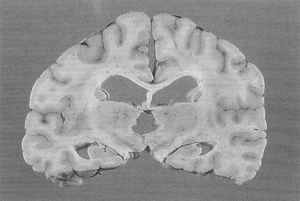

The third chapter concerns "Primary Cerebral Neoplasms as a Cause of Sudden, Unexpected Death" is a very good review of this subject area. There are 42 references, the most recent being 2002. Again, a typo indicating the "brain is drained in buffered formaline for fixation" is a very strange way to both spell formalin and to discuss the placement of the brain in formalin.